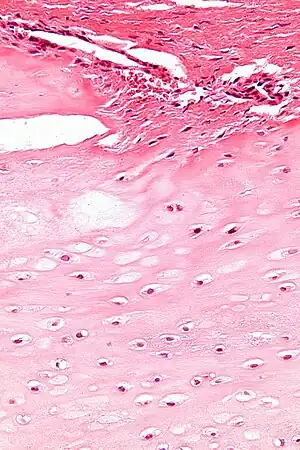

Pathophysiology

Enchondroma is a type of non-cancerous bone tumor that originates from cartilage.[1] An enchondroma most often affects the cartilage that lines the inside of the bones. The bones most often involved with this benign tumor are the miniature long bones of the hands and feet. It may, however, also involve other bones such as the femur, humerus, or tibia. While it may affect an individual at any age, it is most common in adulthood. The occurrence between males and females is equal. It is not very likely that the enchondroma will grow back in the same spot; the rate is less than ten percent.

Diagnosistic tests include medical imaging.[2] Appearances on X-ray show a small lobe-shaped, dark tumor in the middle of the bone.[2] It typically contains white spots; calcified chondroid matrix (a "rings and arcs" pattern of calcification).[2] It does not extend into soft tissues.[6] Magnetic resonance imaging (MRI) and CT scan may be requested to further evaluate the tumor.[8]